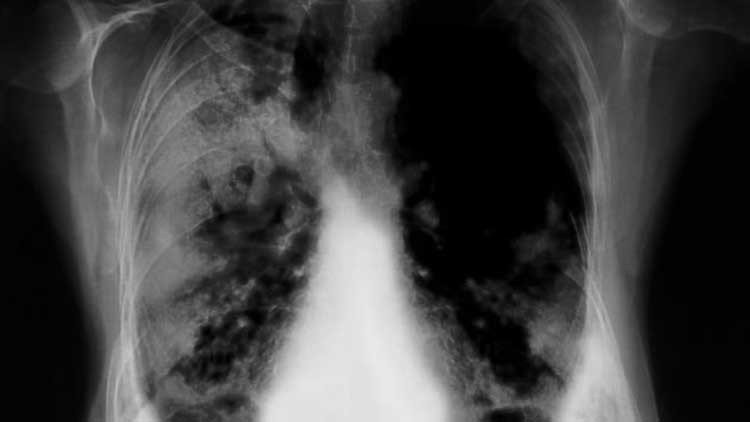

cáncer de pulmón

La cosa sobre la fabricación de grandes cigarros es, que fumarlos son muy, muy malo. El cáncer de pulmón es la cuarta causa de muerte en Cuba. Los médicos de los investigadores del Centro de Inmunología Molecular, trabajaron con el Cimavax durante 25 años antes de que el Ministerio de Salud lo diera al público de forma gratuita en 2011.

Cada inyección cuesta al gobierno alrededor de $ 1. Un ensayo de fase II en 2008 mostró que los pacientes con cáncer de pulmón que recibieron la vacuna vivieron un promedio de cuatro a seis meses más que los que no lo hicieron. Esto llevó a Japón y algunos países europeos comenzar con los ensayos clínicos con el Cimavax también.

Para ser justos, Cimavax probablemente no sea un medicamento contra el cáncer que cambia el juego en su forma actual. La vacuna no ataca los tumores directamente, en su lugar van a una proteína producida por tumores que luego circula en la sangre. Esta acción estimula el cuerpo de una persona para liberar anticuerpos contra el factor de crecimiento epidérmico de una hormona funcionando normalmente controla el crecimiento celular, pero puede también, si se descontrola, causar cáncer. (Mucha gente en general piensa que las vacunas previenen la enfermedad, técnicamente una vacuna es una sustancia que estimula el sistema inmunológico de alguna manera.) Entonces el punto es mantener un crecimiento controlado de los tumores de pulmón y las metástasis con el Cimavax, haciendo su crecimiento lento – algo crónico, pero manejable.